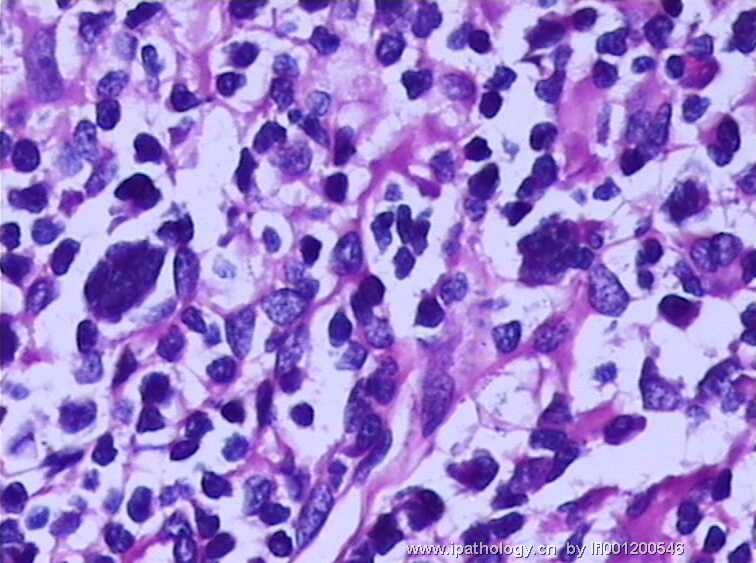

女,45岁,发现颈部多个淋巴结肿大,体查时发现全血细胞减少.取最大的淋巴结送检.

淋巴结结构破坏,有明显异常细胞,结合病史,考虑恶性,淋巴瘤、白血病?不知血片分类怎样?待组化和专家讲解。谢谢!

恶性,考虑淋巴造血系统肿瘤。NHL或白血病。

恶性是肯定,就是要排除转移的恶黑。再考虑原发的非何杰金